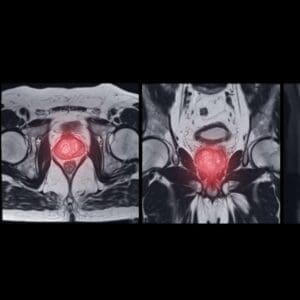

Magnetic Resonance Imaging (MRI)

Magnetic Resonance Imaging (MRI) has been used for many years to evaluate soft tissue, but has only become mainstream for prostate imaging over the last seven to 10 years. Because the prostate is a very dense organ, it was very difficult to visualize with previous MRI machines. Now newer, more powerful magnets—the 3 Tesla (3T)—have significantly improved the images collected.

In 2012, the PI-RADS (v.1) imaging grading system was introduced. This grading system enables radiologists and urologists to grade abnormal areas in the prostate. The PI-RADS scale ranges from 1 to 5 with 5 being the highest rating and indicating areas most likely to harbor a focus of intermediate or high-grade prostate cancer. While the MRI is roughly 80 percent accurate in finding intermediate to high- grade prostate cancer, it often misses lower-grade prostate cancer. This is currently rarely an issue, though, as many of these men are candidates for active surveillance to follow these low-risk cancers without treatment.Not all MRIs are built the same, so it is extremely important to discuss your MRI with your urologist. Urology Partners currently recommends Gateway Imaging in Arlington because they have the MRI and software specifications to produce high-quality images that are compatible with our inVivo Uronav fusion biopsy software system.

MRI Fusion-Guided Biopsy

TRUS-guided biopsies don’t always deliver definitive answers. There have been many cases where men with PSA levels of 20 or 30 have undergone several biopsies that repeatedly come back negative. Their cancer could not be located due to limitations of the TRUS technology. In an effort to get a clearer picture of the prostate and suspicious areas, many men have a prostate MRI before their biopsy, or as a follow-up after a negative biopsy with a persistently elevated PSA.Not all prostate cancer is the same.